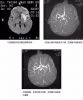

联合头部DWI和MRA在超急性期脑梗死诊断中的作用

目前我院正在开展急性缺血性脑卒中(AIS)规范化治疗项目,作为重要的参与科室,下面和大家共同探讨学习一下磁共振弥散加权(DWI)和血管成像(MRA)在超急性期脑梗死诊断中的作用和意义。急性脑梗死是老年人常见病,近年来曾上升和低龄化趋势,严重...

时间就是大脑

图1脑梗死模式图图2缺血半暗带模式图急性脑梗死具有非常高的致残率和致死率,当脑血管发生堵塞后,由于脑血管远端支配的脑组织发生缺血缺氧,5分钟内脑血流未恢复即可导致不可逆的脑细胞死亡,而每缺血1分钟会造成200万个脑细胞死亡,因此对于急性脑梗...